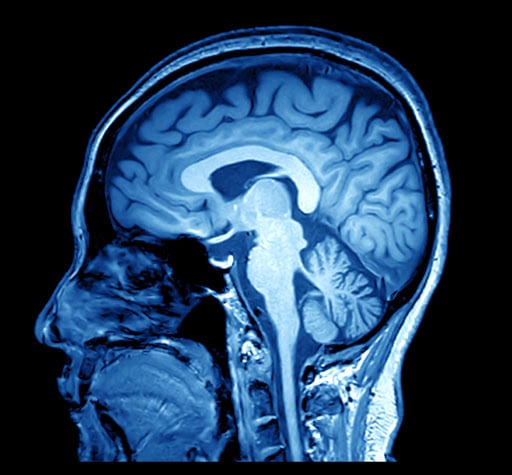

But what is that something that music does to the human brain? Fortunately, there is no shortage of college students willing to lie in an MRI machine and listen to music for long periods of time in exchange for pizza money.

Daniel Abrams of Stanford University shoved numerous participants into MRI machines and discovered that music activated parts of the brain involved in “movement, planning, attention, and memory.” That explains why you still know every single lyric to Don McLean’s “American Pie”!

That’s not all music does in the human brain. Neuroscientist Valorie Salimpoor discovered that music stimulates the release of dopamine in the brain. You may have heard dopamine called “the feel-good hormone.” It tends to show up when humans are doing things that cause pleasure, like gambling, eating, and enjoying some quality time in the bedroom.

Not exactly, but it definitely arouses the brain. What these studies show is that music can grab our attention and pluck our emotional chords like a violin. No wonder music for filmmakers can be an incredible tool! How can filmmakers use the powerful psychological effects of music to make their movies even better?